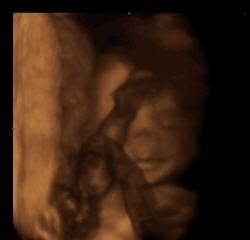

Aufnahmen aus der 16. Schwangerschaftswoche. Die Scheitel-Steiß-Länge beträgt ca. 9,4cm. |